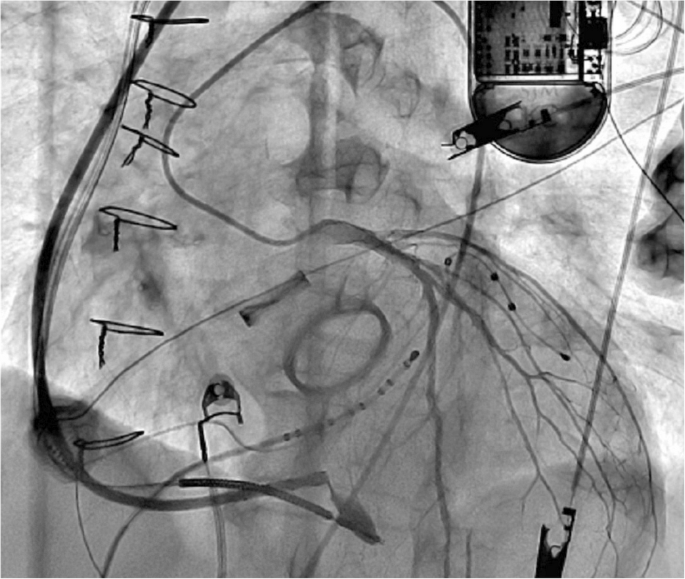

手术在全身麻醉下进行,通过左侧锁骨下静脉穿刺将LBBAP导管送入右心室。手术过程中使用LBBAP导管和三维弯曲传导导管进行引导。Tendril 2088TC 58厘米长的导线(St. Jude Medical)在确定正确的间隔穿刺位置(距离心尖和心底等距)后,通过LBBAP方法进行插入,并持续监测12导联QRS波形和单极阻抗。通过不透明造影剂确认导管位于室间隔边缘(视频1)。

为了降低动脉损伤的风险,在通过左前降支(LAD)的间隔分支时,通过插入左主干冠状动脉(LMCA)开口的6F Judkins导管注入不透明造影剂来进行可视化观察(视频2,图2)。在间隔映射过程中,当以100毫米/秒的频率进行起搏时,在V1导联观察到W形波形(图3